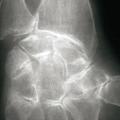

La forme pseudorhumatoïde est rare (5 %), simulant une polyarthrite rhumatoïde (diagnostic différentiel), avec parfois des signes systémiques d’inflammation (élévation de la vitesse de sédimentation et de la CRP). Le diagnostic repose sur la mise en évidence des cristaux de PPC. La radio peut mettre en évidence des calcifications des cartilages articulaires (fig. 6) et des fibrocartilages (fig. 7, 8, 9 et 10). L’échographie (plus sensible) peut mettre en évidence des dépôts de PPC, qui apparaissent comme une fine bande hyperéchogène au sein des cartilages hyalins et comme des points scintillants dans les fibrocartilages ou dans la membrane synoviale. Dans l’arthrite chronique à PPC, lespossibilités thérapeutiques sont, par ordre de préférence : colchicine (de 0,5 à 1 mg/j), petites doses de cortisone, parfois les AINS per os (mais leur prescription est souvent limitée par les comorbidités chez les patients âgés), méthotrexate et l’hydroxychloroquine. Il n’y a pas aujourd’hui de traitement « de fond », mais des molécules sont à l’étude.